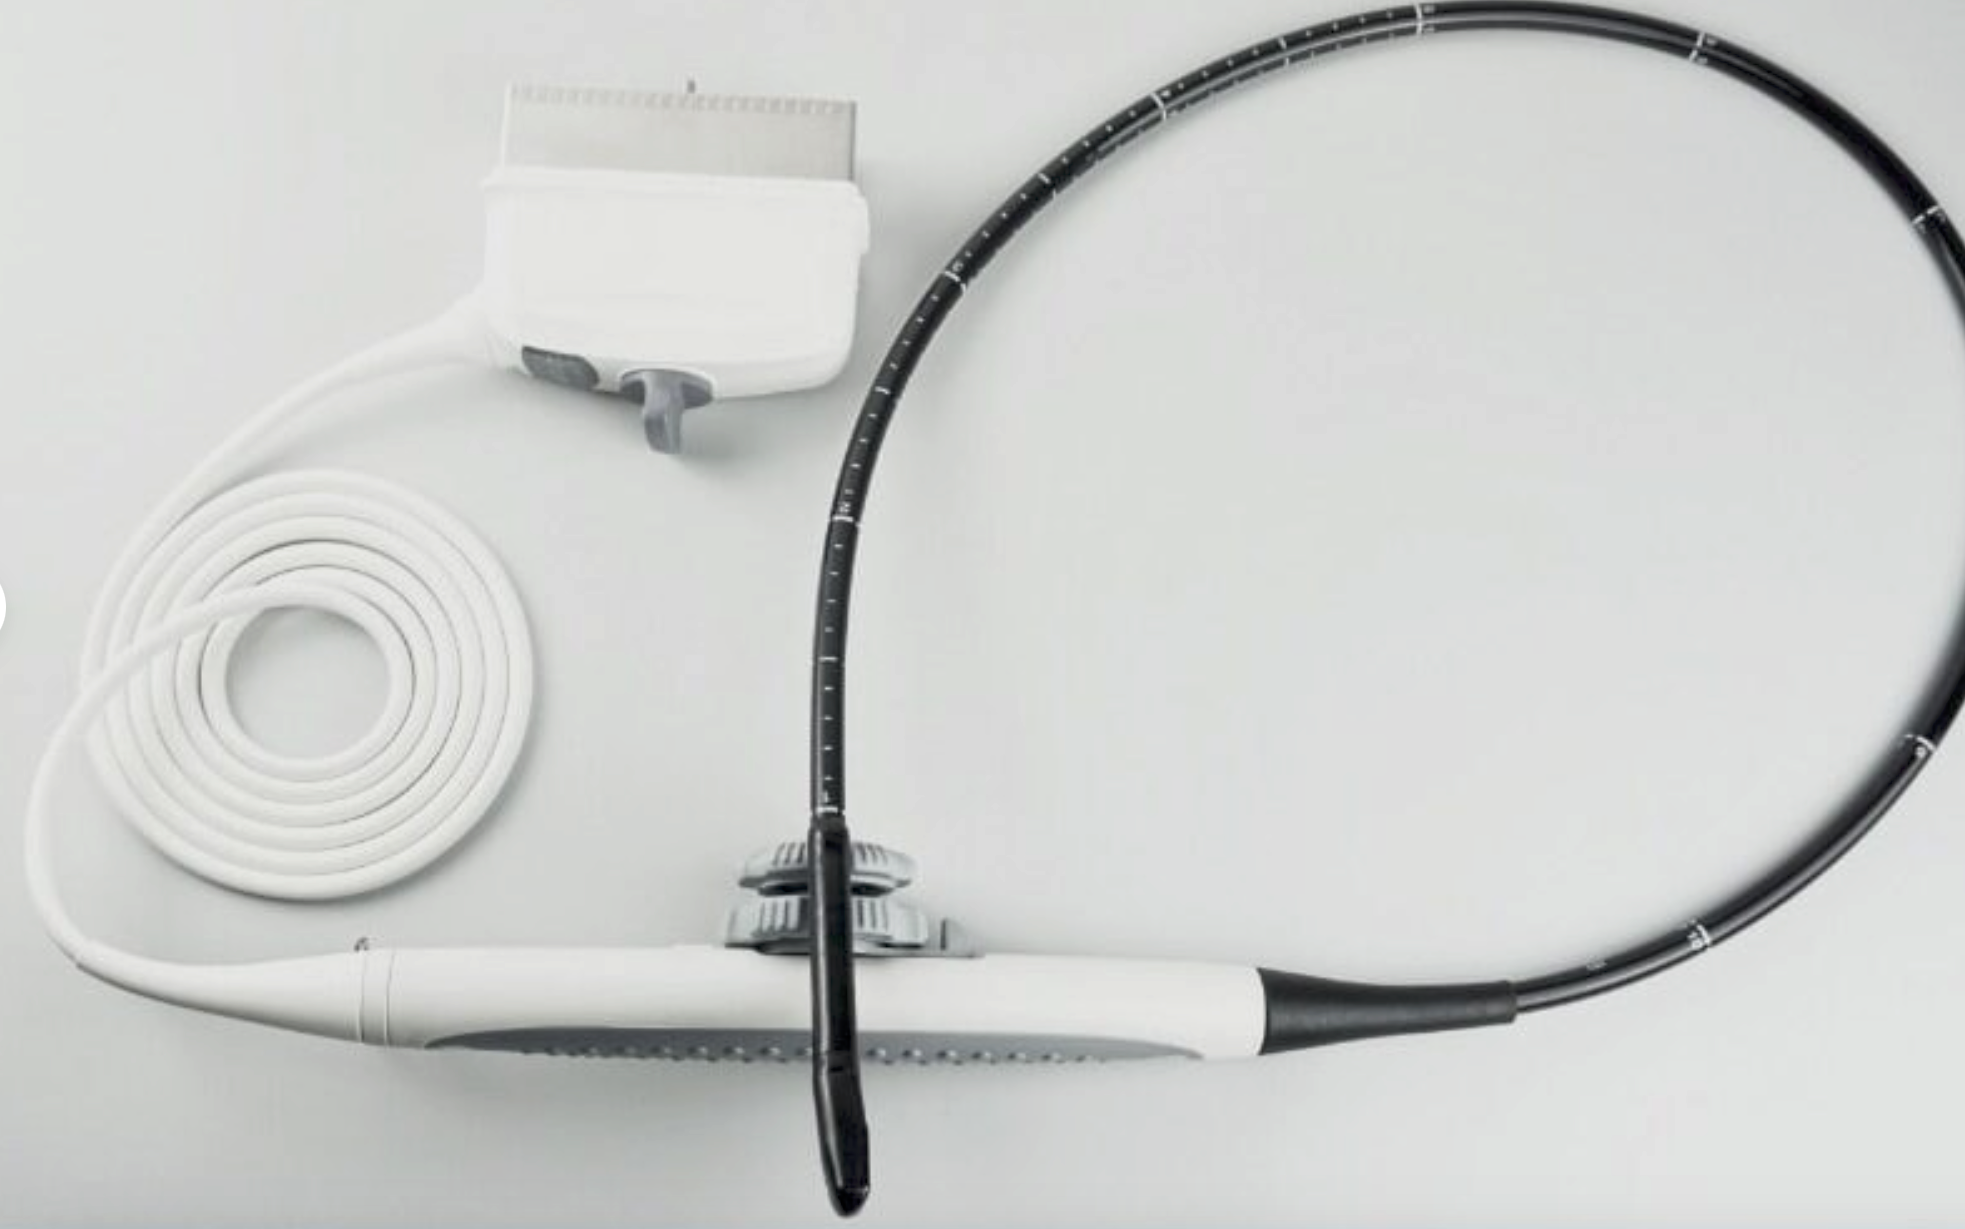

The Laptop Ultrasound Scanner is designed to provide clear and precise imaging, making it an essential tool for healthcare professionals. This device offers advanced functionality, allowing doctors to perform a wide range of examinations. Because it includes a transvaginal probe, it is particularly effective for gynecological assessments, ensuring accurate diagnosis.

Portability and Convenience

One of the standout features of this ultrasound machine is its portability. The compact design, combined with a carrying case, makes it easy to transport between clinics or even to home visits. This ensures that medical professionals can deliver timely care, regardless of location. Therefore, it’s perfect for practitioners who need versatility in their equipment.